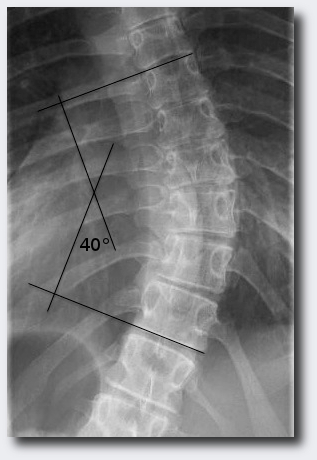

The diagnosis scoliosis is made by a doctor or an naturopath ("Heilpraktiker"). Usually a X-ray of the spine is used for that. Optimal is it if the doctor can make one x-ray of the whole spine, but there are not many doctors who have this possibility. One can measure on the xray how strong the spine is bent and how many degree each curve shows. |